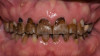

At a clinic treating patients in an underserved population, a 54-year-old female patient presented requesting extraction of all of her teeth and fabrication of dentures for her long-term restorations. The patient had a history of breast cancer, which had been treated with chemotherapy. She believed that full dentures would be an appropriate treatment option for her, owing to the poor state of her oral health and dentition and because she had limited financial resources and did not think that she could afford restoration of her teeth. The patient reported that she had experienced depression and alcohol abuse because of her cancer diagnosis, and that she had neglected her dental care during the course of her cancer treatment, resulting in generalized moderate-to-severe caries with moderate wear due to bruxism (Figure 1 through Figure 5). She also presented with significant staining of her remaining dentition due to the alcohol abuse.

Fig. 1